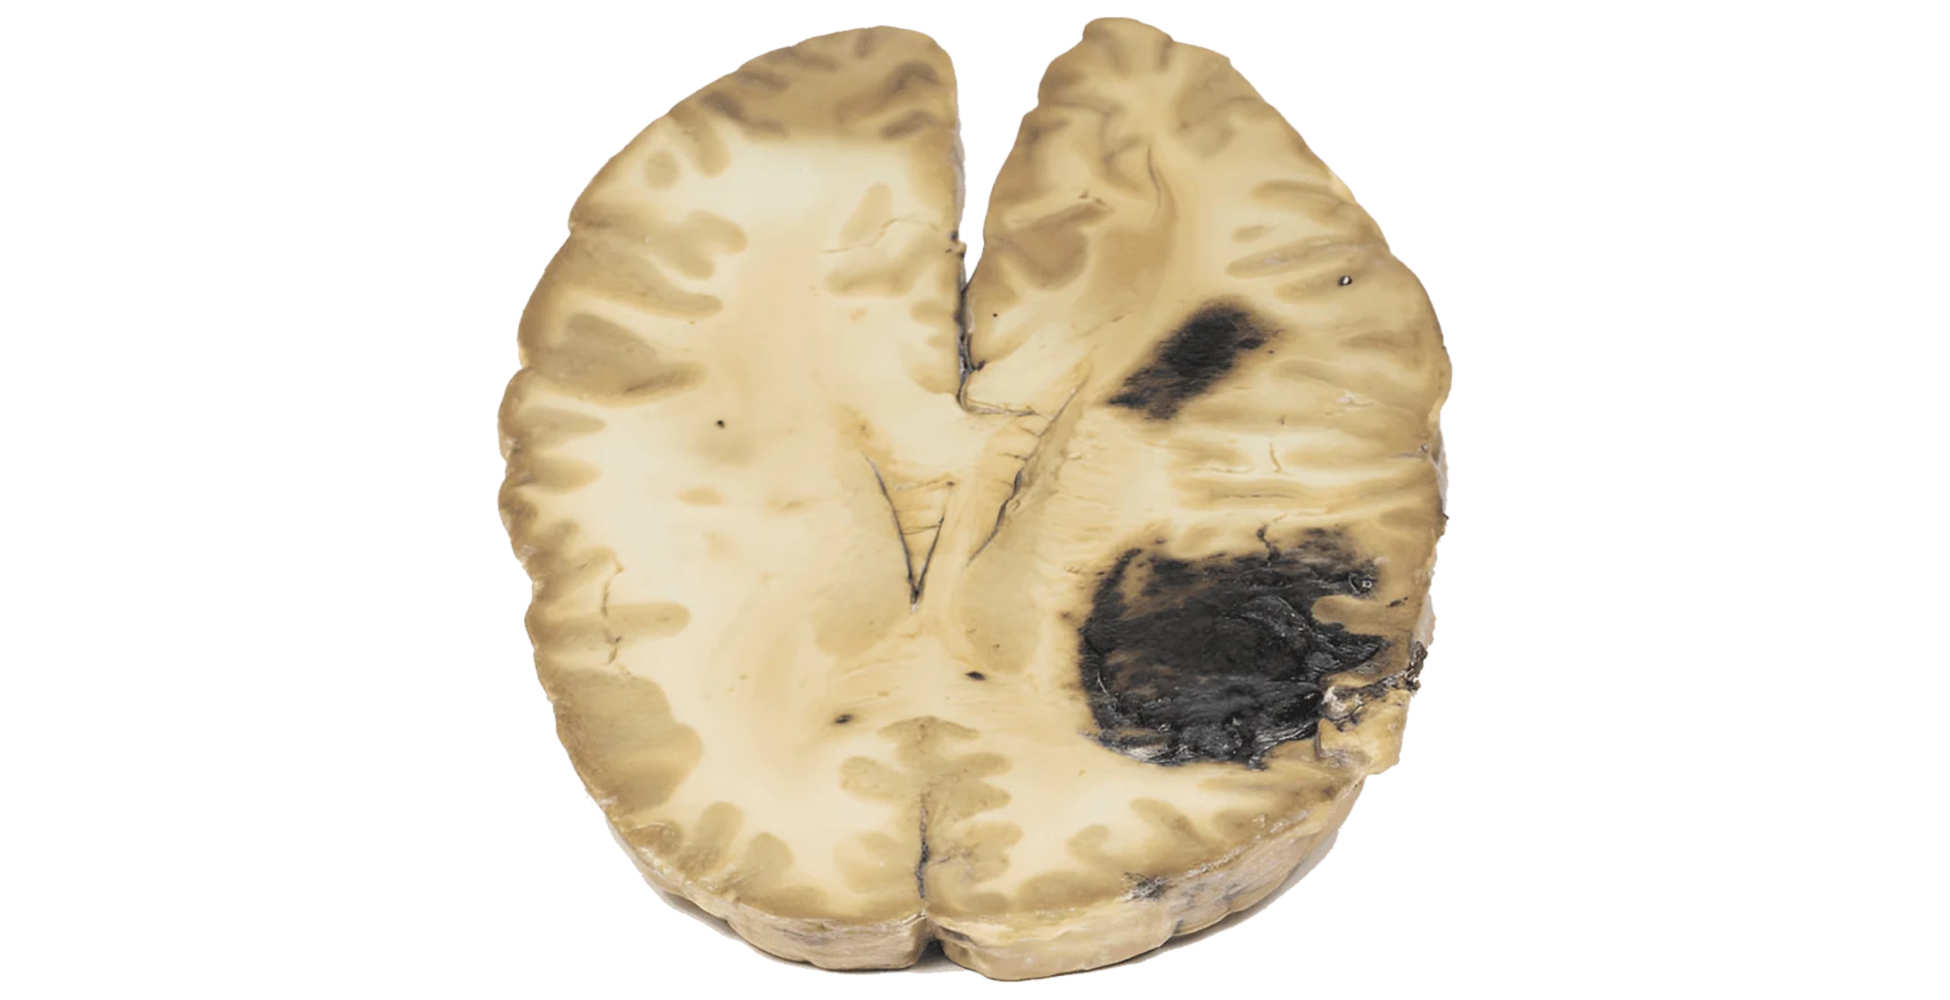

La sección horizontal del cerebro muestra:

- Dos grandes hemorragias intraparenquimatosas en los lóbulos frontal y parietal derechos

- Cada lesión mide aproximadamente 5 cm

- Múltiples focos hemorrágicos pequeños distribuidos bilateralmente en la sustancia blanca

Este patrón es característico de hemorragias cerebrales múltiples secundarias a trastornos de la coagulación.